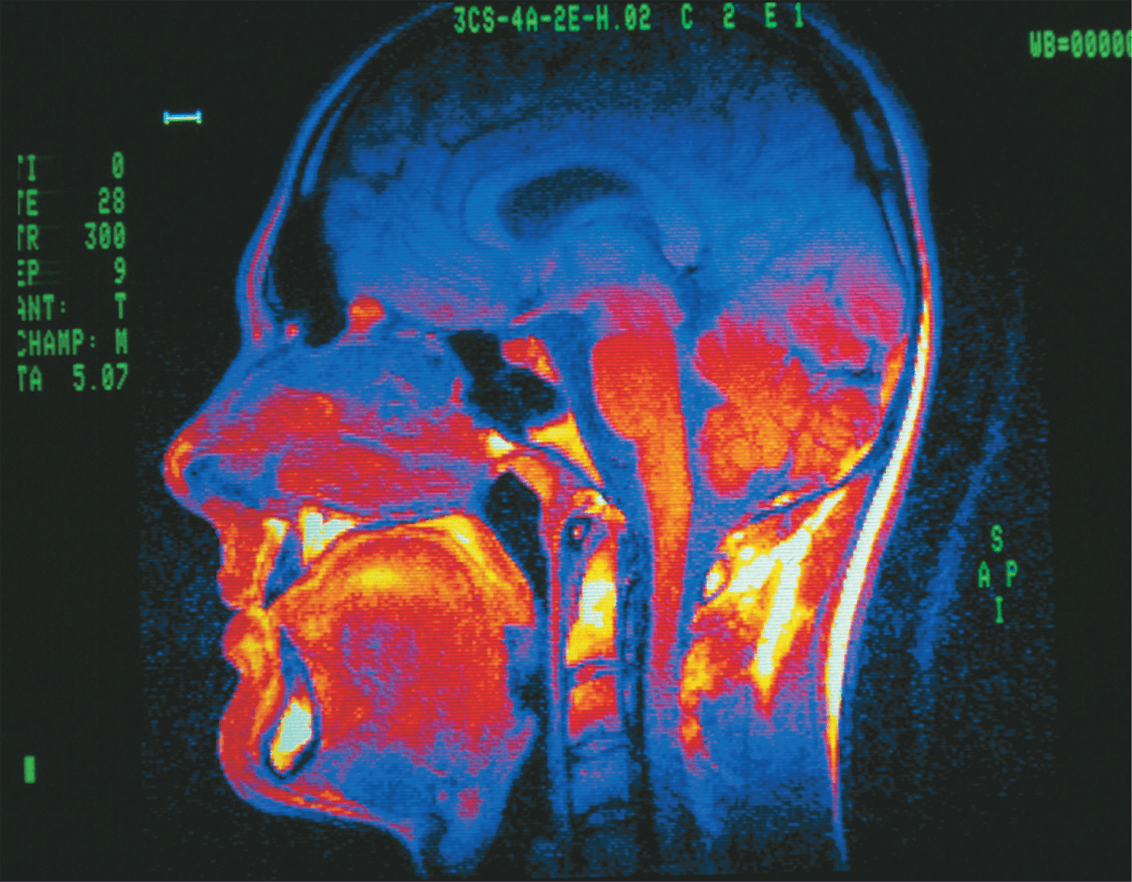

What type of image is this, what kind of tissues and where in the body can it be used?

MRI; soft tissues; any plane of the body